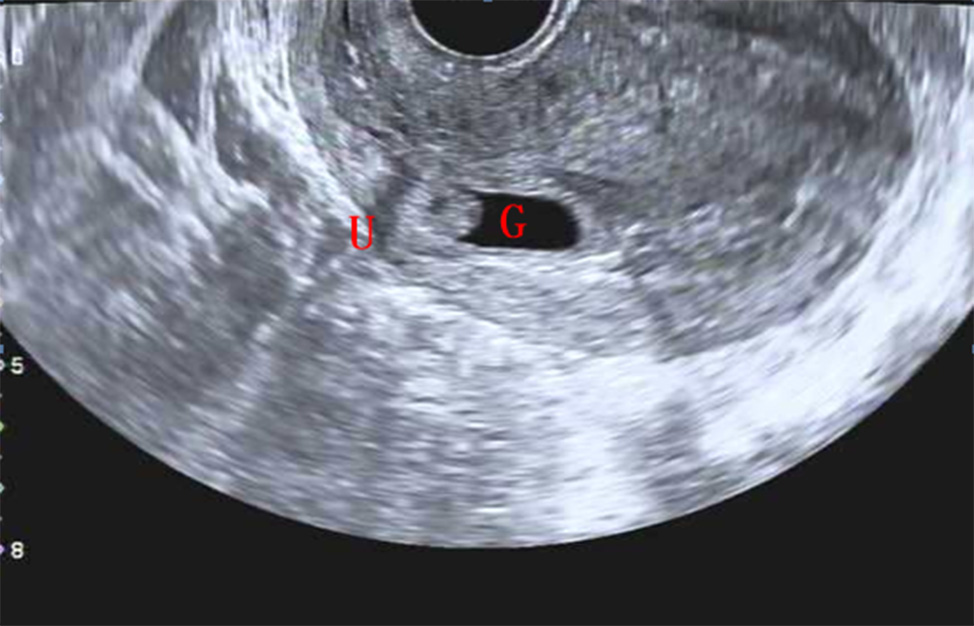

Siêu âm qua ngả âm đạo cho thấy túi thai bám vào vết sẹo tử cung và xâm lấn vào lớp cơ. Ảnh: imrpress